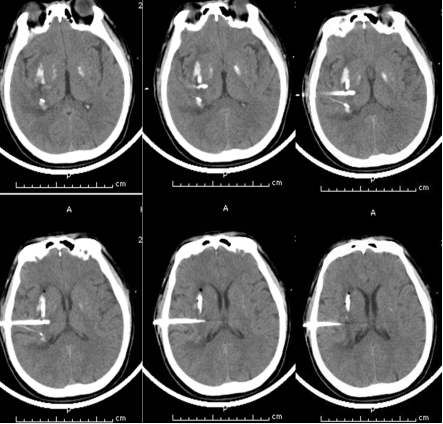

术前

术中

术 后

内镜下血肿清除术具有创伤小,血肿清除快速彻底、可直视下可靠止血、可清除深部及脑室内血肿等优点